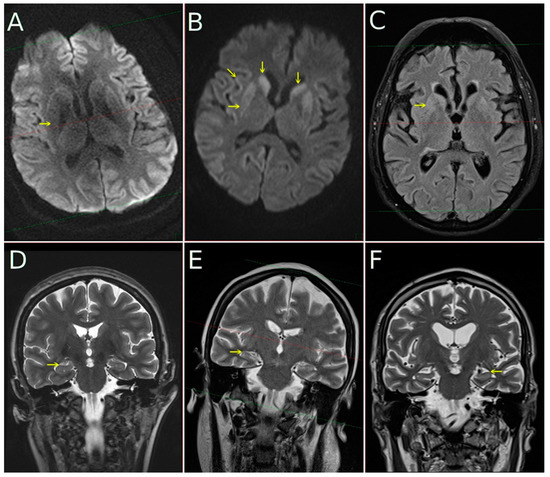

3.4. MRI Results

MRIs were available in 206 cases (95.81%), and FLAIR/DWI sequences were available in 188 of these (87.44%; for detailed information, see Table 1). Typical FLAIR and DWI findings meeting the WHO diagnostic criteria for probable CJD were found as follows: cortical hyperintensities in 146 of 188 cases (77.66%), basal ganglia (caudate and putaminal) hyperintensities in 122 of 188 cases (64.89%), and both cortical plus basal ganglia hyperintensities in 109 of 188 cases (57.98%). Manifest mesial temporal atrophy (Scheltens MTA score 2) was present in 32 of 206 cases (15.53%), severe parieto-occipital atrophy (Koedam score 2) was present in 22 of 206 cases (10.68%), and potentially clinically relevant ischemic subcortical white matter lesions (Fazekas score 2 and 3) were present in 32 of 188 cases (17.02%). For detail see Figure 1.

Figure 1. MRI in CJD subjects performed at 1.5T field strength: diffusion-weighed images ((A,B), DWI) with b-factor 1000, FLAIR image (C), coronal T2-weighted images (DF). In the first column (A,D) data from subject with pure CJD—no DWI hyperintensity in putamina (arrow) is present and MTA is 0 (read as normal). In the second column (B,E) subject with tau comorbidity with mild hippocampal atrophy (MTA 1, arrow on (E)) and DWI (B) hyperintensity in putamina (horizontal arrow), caudates (vertical arrows) and with cortical ribboning (oblique arrow). In the third column (C,F) subject with CJD and AD comorbidity is shown. A moderate hyperintensity is visible not only on DWI (not shown), but as well on FLAIR image (C). Hippocampal atrophy is well pronounced, MTA 2 (arrow from right side of the (F), pointing to the left hippocampus which manifests clear atrophy).